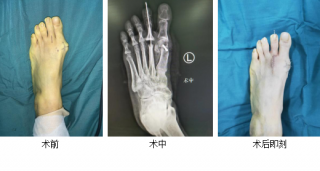

第三代微创踇外翻矫正手术

仁慈足踝团队采用4毫米低频超声骨刀微创截骨,切口很小无需缝合;低频超声骨刀锋利、精准、自带注水降温,能更好地保护骨骼血运,使得截骨处更快愈合,手术基本无血渗出,完美修整踇外翻,术后第二天就能下地行走。

仁慈足踝科40分钟完成10多年踇外翻微创矫形手术

42岁的吴女士,发现左足踇外翻10多年,最近两月感觉左足疼痛,穿较紧的鞋子时尤其明显,且疼痛日渐加重,影响日常行走

详细 >>